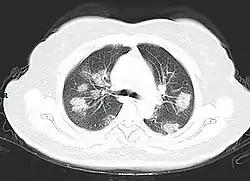

Imaging

Chest CT scans may be helpful to diagnose COVID-19 in individuals with a high clinical suspicion of infection but are not recommended for routine screening.[93][105] Bilateral multilobar ground-glass opacities with a peripheral, asymmetric, and posterior distribution are common in early infection.[93][106] Subpleural dominance, crazy paving (lobular septal thickening with variable alveolar filling), and consolidation may appear as the disease progresses.[93][107] Characteristic imaging features on chest radiographs and computed tomography (CT) of people who are symptomatic include asymmetric peripheral ground-glass opacities without pleural effusions.[108]

Many groups have created COVID-19 datasets that include imagery such as the Italian Radiological Society which has compiled an international online database of imaging findings for confirmed cases.[109] Due to overlap with other infections such as adenovirus, imaging without confirmation by rRT-PCR is of limited specificity in identifying COVID-19.[108] A large study in China compared chest CT results to PCR and demonstrated that though imaging is less specific for the infection, it is faster and more sensitive.[92]

A CT scan of a person with COVID-19 shows lesions (bright regions) in the lungs